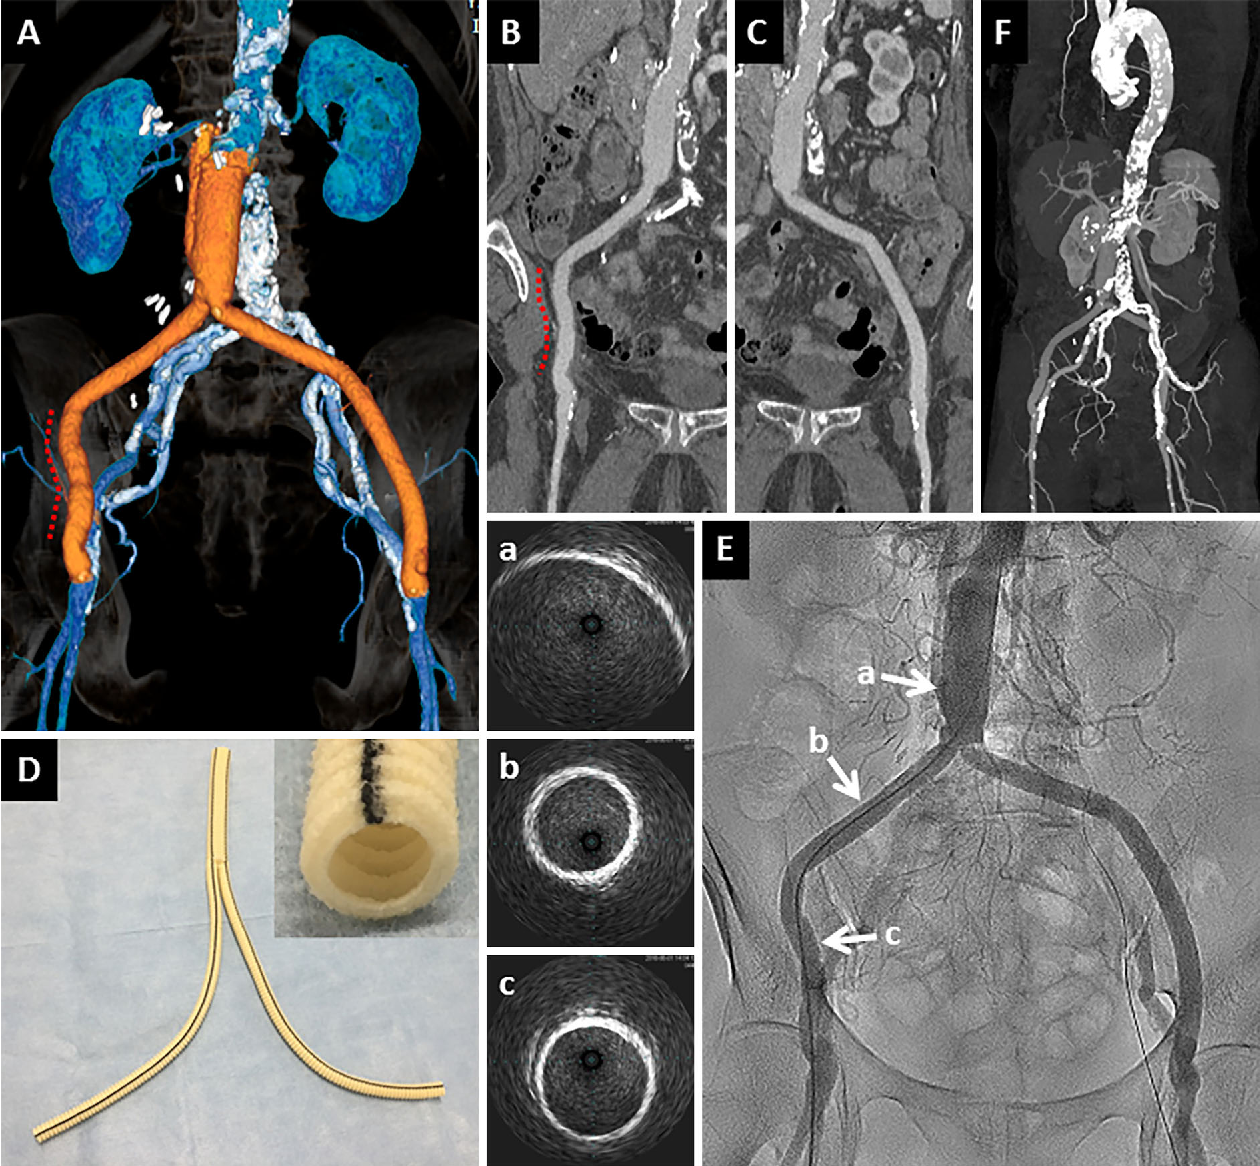

Recognizing the early signs of an infected wound is critical for proper healing. Learn to identify key symptoms like redness, swelling, pus, and fever. Understand when to seek medical attention for bacterial infections, how to monitor healing progress, and the essential first-aid steps to prevent complications and promote faster recovery. Don't ignore these warning signals; stay informed today.